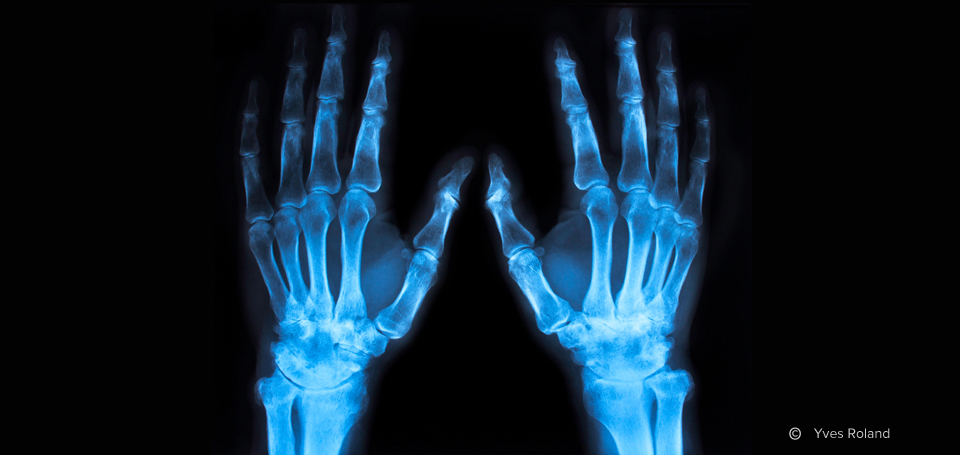

Konventionelle Röntgenuntersuchungen stellen nach wie vor die Basisuntersuchung oder Verlaufsuntersuchung bei bestimmten Krankheitsbildern wie Knochenbrüchen oder Lungenentzündungen dar. Modernste, ständig geprüfte Röntgengeräte garantieren die derzeit mögliche niedrigste Strahlendosis. Röntgenstrahlen werden hierzu durch den betreffenden Teil des Körpers gesandt und von den einzelnen Strukturen im Körper – Knochen, Gewebe oder Luft – unterschiedlich absorbiert und als unterschiedliche Schattierungen auf der Röntgenaufnahme abgebildet.